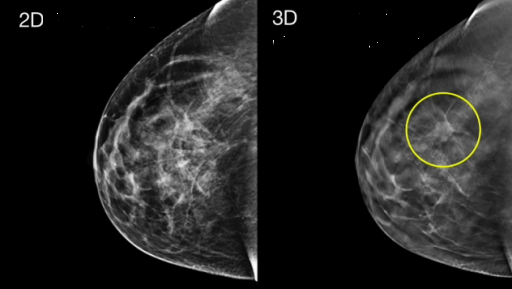

Рак молочных желез занимает первое место среди злокачественных заболеваний женщин. К настоящему времени разработано множество диагностических методов, один из которых - цифровая рентгеновская маммография. Это рентгенологическое исследование молочных желез для выявления опухолей или кист. Его информативность составляет 75-99 %. А всем известно, что чем раньше выявлено заболевание, тем легче его лечить.

В возрасте около 40 лет каждой женщине рекомендуется сделать первую маммограмму. Между 40 и 50 годами женщины должны проходить маммографию каждые год-два. После 50 лет все женщины проходят маммографию ежегодно. Женщины с высоким риском рака молочных желез должны проходить маммографию ежегодно, начиная с 35 лет.